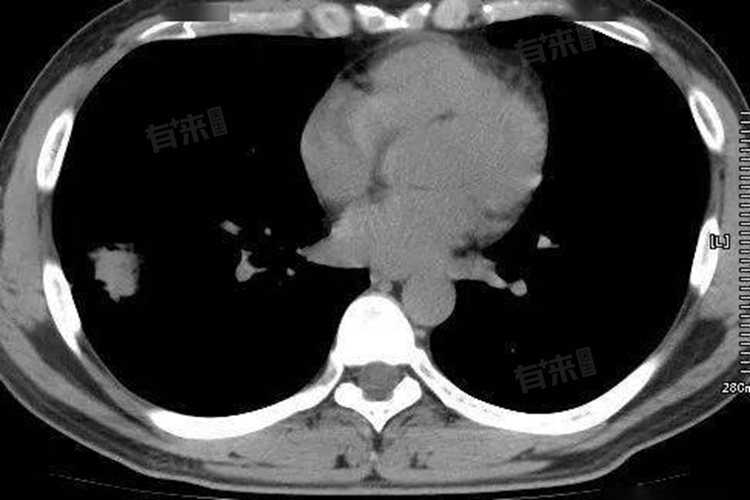

周围型肺癌是指发生于三级支气管以下、呼吸性细支气管以上的肺癌,肿瘤位于肺段支气管远端,贴近肺膜,以腺癌居多,CT影像表现多样,包括通常为类圆形或不规则肿块,边界不光整。

- 多呈类圆形或不规则形肿块,这与肿瘤细胞不均衡生长、浸润周边组织有关。相较于良性病变规则的圆形、椭圆形外观,周围型肺癌边界常不光整,边缘可有分叶征,这是因肿瘤各部位生长速度差异所致,以腺癌出现分叶征较为多见。

- 除分叶征外,还常见毛刺征,毛刺为短而细的线状影,从肿块边缘向周围肺组织伸展,如同刺猬身上的刺,反映肿瘤呈浸润性生长,致使周边肺间质反应、纤维结缔组织增生。

- 密度通常不均匀,内部可见坏死、囊变区,肿瘤生长迅速,中心部分血供跟不上需求,就会出现缺血坏死,在CT图像上呈低密度灶;部分还能发现空洞,空洞内壁多不规则,有壁结节附着,与肿瘤组织坏死后排出有关。

- 增强扫描时呈不均匀强化,因肿瘤内血管分布杂乱、部分区域坏死无强化,强化后肿瘤实质部分CT值明显升高,有助于和少血供的良性病变鉴别。